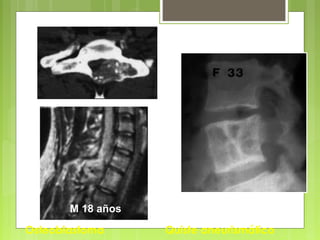

Osteoblastoma Quiste aneurismático

M 18 años

Argumentos topográficos  Columnavertebral  Granulomas eosinófilos  Angiomas, quistes aneurismáticos, osteoblastomas, cordomas  Huesos planos  Granulomas eosinófilos  Huesos de la mano  Condromas  Localización plurifocal  Displasia fibrosa, condromatosis osteocondromatosis

• 125.

Evolución: La curaciónse obtiene en caso de la exéresis completa del nido